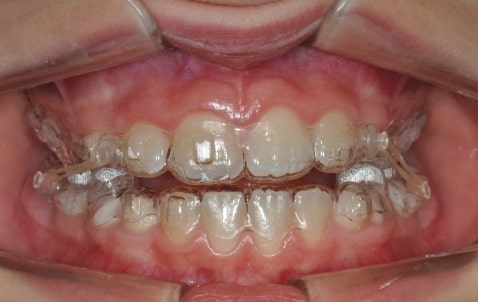

Malocclusion A6 Correction of Mandibular Retrusion in Growth phase patient | Skeletal Class II | Class II Division 1 malocclusion | Deep bite | Mixed dentition

Initial Photos and datas

Clinical examination and diagnosis

DENTAL:

- Molar and Canine class 2 on the right side – Molar and Canine clss 1 on the left side

- Upper diastema (11-21)

- Increased Overjet

- DeepBite

- Reduced Transversal Diameters

- Deviated Lower Midline 2 mm to the Right